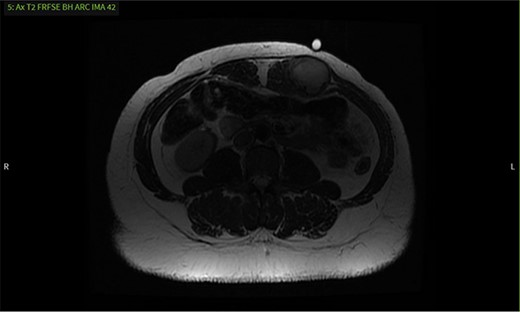

CT, ultrasound and MRI were obtained, revealing a 4.3 × 3.3 × 4.1 cm mass embedded in the left rectus muscle (Figs 1–3). Based on the MRI showing hyperintensity on T2 sequence and hypointensity on T1, we predicted the mass was a benign intramuscular myxoma. Informed consent was obtained and risks of the proposed surgical plan were explained. We proceeded with surgery to obtain a pathological diagnosis and curative resection. Under general anesthesia, the mass was resected with relatively free margins and only a small amount of underlying musculature was taken (Fig. 4). Knowledge of the abdominal wall anatomy was critical to avoid entry into the peritoneal cavity and potential compromise of its integrity. The soft tissue defect was reinforced using STRATTICE™ acellular dermal matrix mesh. Microscopic examination and immunohistochemistry diagnosed the mass as a desmoid tumor with negative margins and no evidence of malignancy (Figs 5 and 6). The patient was discharged and progressed well postoperatively.

MRI shows a mass with well-defined margins and high signal intensity on T2 sequence.

It was difficult to delineate whether the mass was primarily cystic or solid based on the initial CT, so an ultrasound was ordered. The ultrasound revealed the mass had enlarged, now measuring 5.7 × 3.6 × 4.7 cm. Internal vascularity was present, making the diagnosis of a solid mass more likely than a seroma (Fig. 2). An MRI redemonstrated the mass embedded in the left rectus muscle (Fig. 3). It had well-defined margins with high signal intensity on T2 sequence and low signal intensity on T1. On post-contrast sequences, the mass had homogeneous enhancements and a thick enhancing wall, most compatible with an intramuscular myxoma. However, without tissue biopsy, other solid tumors could not be dismissed, such as desmoid.